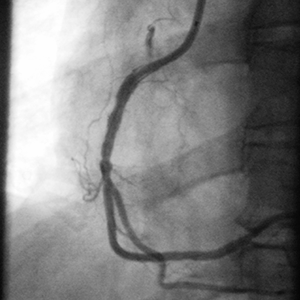

• La angiografía inicial no mostró una enfermedad significativa del sistema coronario izquierdo.

• La arteria coronaria derecha (RCA) presentaba un alto grado de estenosis con un segmento proximal prolongado de enfermedad.

• La función ventricular izquierdo era normal.

• La angiografía demostró un implante no óptimo del stent debido a calcio no observado en la parte proximal de la lesión.